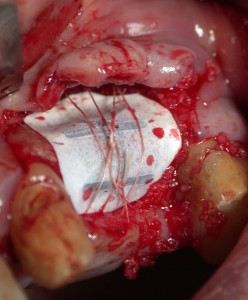

インプラントを1本入れたが、その隣は骨が吸収していて造骨が必要だった。

インプラントを1本入れたが、その隣は骨が吸収していて造骨が必要だった。

喫煙者の造骨は鬼門(その1)